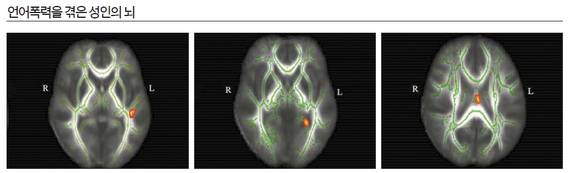

언어폭력이 정작 무서운 이유는 뇌 구조 자체에 악영향을 미치기 때문이다. 감정·언어를 담당하는 영역을 줄어들게 만드는 것이다. 하버드의대 연구진과 국내 연구진(가톨릭의대 최지욱·KAIST 정범석 교수)으로 이뤄진 공동연구팀이 진행한 연구결과는 언어폭력이 정신장애로 이어질 수 있다는 점을 보여준다. 연구팀은 언어폭력의 영향 평가를 위해 건강한 성인 1271명을 대상으로 연구를 진행했다. 그리고 이 중 특히 부모로부터 언어폭력을 심하게 받으면서 자랐지만 딱히 치료를 받지 못한 16명을 가려낸 뒤 이들의 뇌 영상을 정상인 16명의 것과 비교 분석했다.

그 결과 뇌의 백질 영역에서 두 집단 간에 차이를 보였다. 언어폭력에 노출된 집단의 백질 경로가 정상 집단에 비해 좁아져 있는 것으로 나타난 것이다. 백질은 뇌 내부에서 각 영역을 구조적으로 연결하면서 언어 기능과 감정조절 기능을 담당한다. 이 경로가 좁아졌다는 것은 그만큼 기능이 떨어졌다는 것을 뜻한다. 즉, 언어폭력을 지속적으로 받으면 말을 하거나 이해하는 능력이 떨어지고 우울·불안 위험이 크다는 결과다. 특히 연구진은 언어폭력에 노출되는 것이 가정폭력을 목격하거나 성적 학대에 노출되는 것 못지않게 심각한 후유증을 유발한다고 밝혔다. 언어폭력의 심각성이 성적·신체적 학대보다 덜하지 않다는 얘기다.